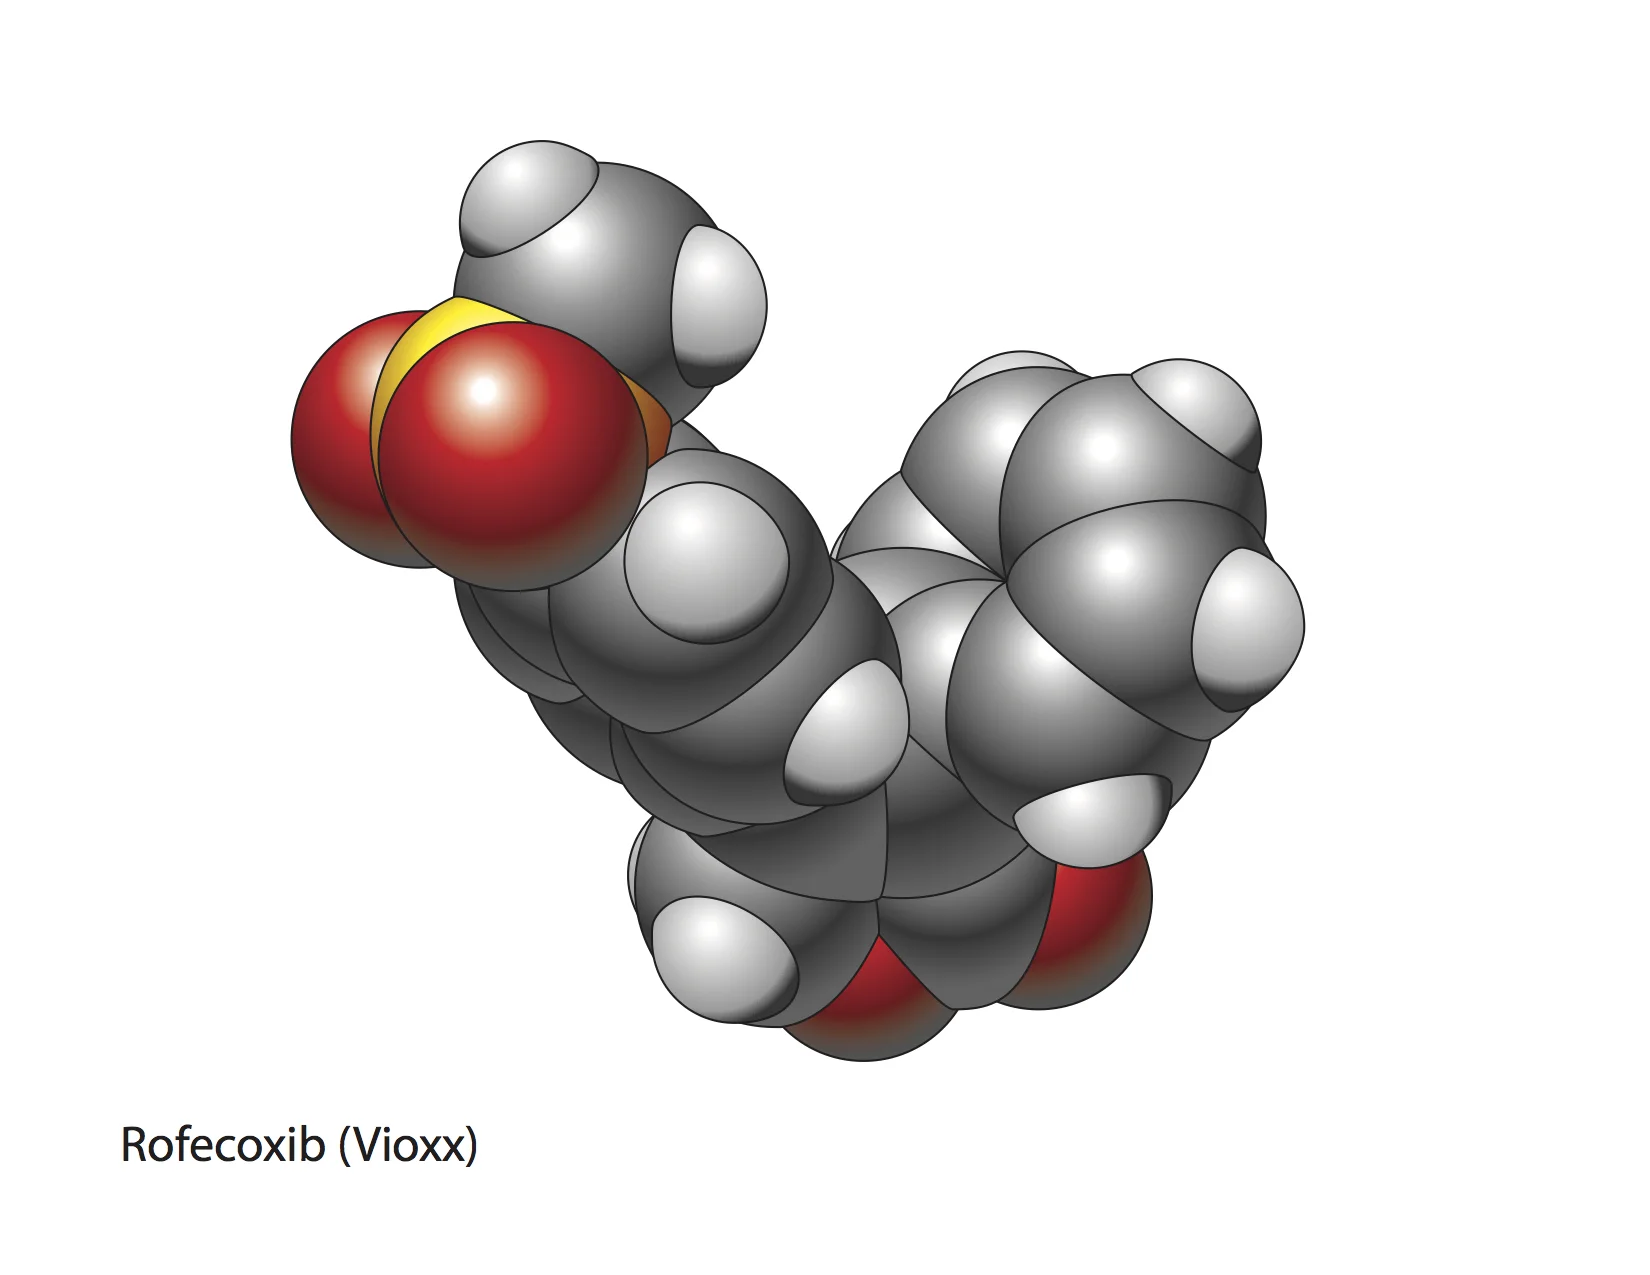

Biomedical art is a form of biological illustration that helps record and disseminate medical, anatomical, and related knowledge. It translates complex technical medical information into visual artwork to support research, patient care and education, public relations, and marketing objectives.